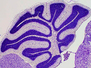

Essential for Life

Cytoskeleton protein ARPC5 is important for prenatal development and for function of the immune system after birth – inheritance of a faulty ARPC5L gene causes early-onset immunodeficiency